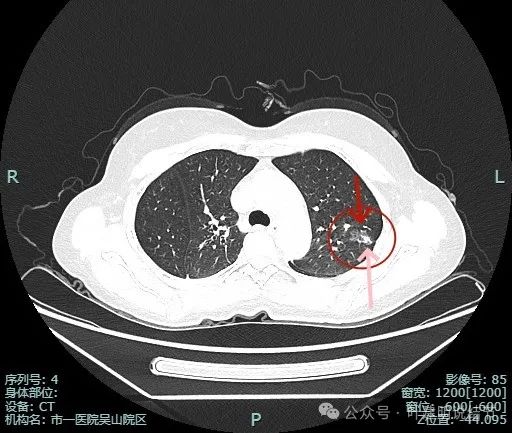

明明典型浸润性癌影像表现病理结果却是原位癌,原位癌也可表现为混合密度?

病史摘要:患者 3 个月前社区体检发现肺结节,就诊时医生考虑左上病灶基本为肺癌且倾向浸润性,因首次发现,建议口服抗炎 10 - 12 天,间隔 3 个月复查。此次复查无吸收好转及明显进展,拟手术治疗。诊疗过程:体格检查未提及。影像检查显示左上叶胸膜下混合密度结节,有血管弯征、胸膜牵拉等诸多恶性特征,下叶有次病灶。临床考虑左上叶病灶恶性且浸润性癌可能性大,建议手术。术中快速切片报腺癌

原位癌